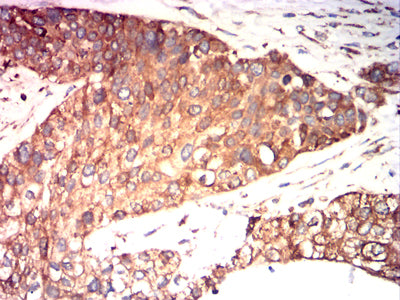

Immunohistochemical analysis of paraffin-embedded human ovarian cancer tissues using P4HB mouse mAb with DAB staining.